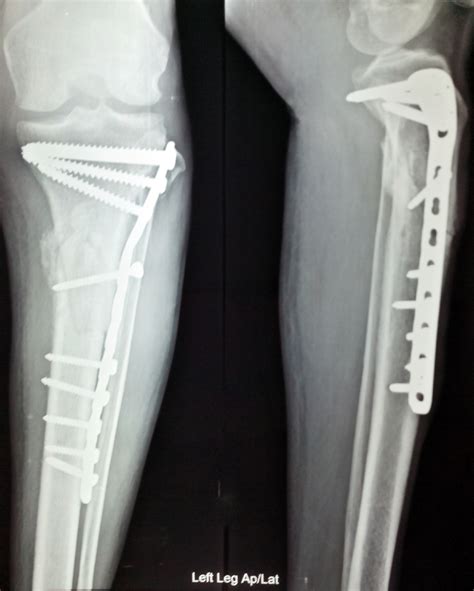

Fracture Set Upgrades Are Making Orthopedic Surgeries Much Faster Now